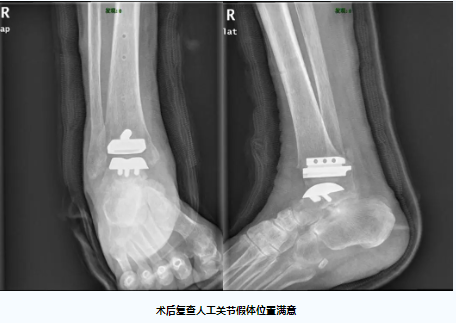

在麻醉手术中心医护团队的精心配合和支持下,经过3个小时的手术,团队成功为高先生植入了全新的踝关节假体,手术出血仅150ml,术后患者疼痛明显缓解,踝关节活动度得到了显著的改善,术后复查的踝关节置换假体位置良好。

人工踝关节置换术是足踝外科领域难度最高的手术之一,标准化的人工关节假体设计精巧,手术操作复杂,手术失败的风险高,对主刀医生的操作有着极高的要求。据文献报道,不少患者因置换手术失败或术后效果不满意而不得不再次行踝关节融合手术进行补救。目前,粤西尚未见独立开展标准化人工踝关节置换术的报道,本次踝关节置换手术取得了良好的治疗效果,得益于关节外科团队巧妙运用了数字骨科3D术前规划技术为高先生进行详尽的计划,有效地避免了许多常见的技术陷阱,本次手术的成功实施,标志着我院足踝外科的人工关节置换技术达到了省内先进水平。